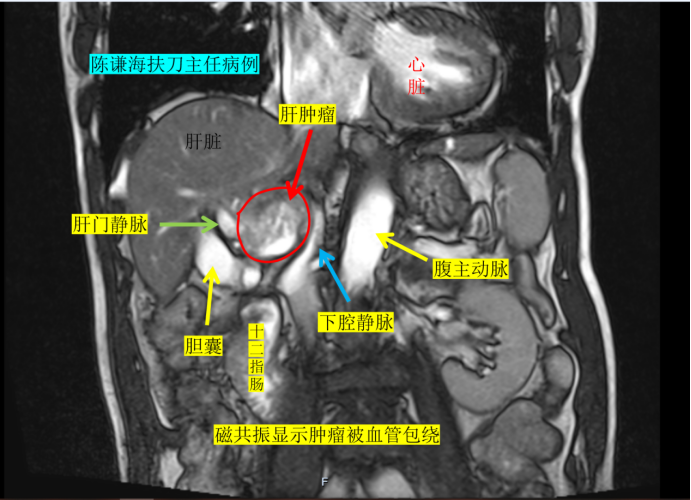

复查增强磁共振结果显示,老人的肿瘤位置极为刁钻——紧邻门静脉、下腔静脉,旁侧是胆囊,头侧靠近肝静脉。如此复杂的病灶环境,让常规消融治疗陷入困境:治疗风险极高,不仅极易损伤周边重要血管,还可能累及胆囊、肠道等邻近器官,治疗方案一度难以推进。

幸运的是,手术过程十分顺利,术中消融效果达到预期。术后复查增强磁共振显示,病灶实现消融满意,门静脉、下腔静脉、肝静脉等重要血管均未受损伤,老人术后第二天便顺利出院,恢复情况超出预期。